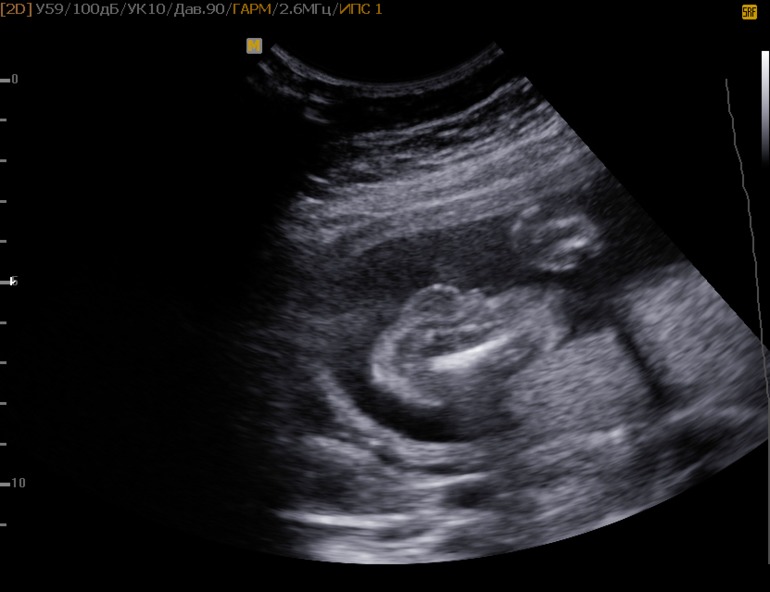

Подскажите кто в животике?!?!!

Вопросы про УЗИ, обследования и анализы: что, где, как, когда?Девочки, была на УЗИ в 18 недель, сказали девочку ждем, а в 21 неделю опять отправили на УЗИ (из за тонуса), в этот раз сказали, что мальчик....... Но ОЧЕНЬ хочу доцю, и не перестаю надеяться, что врач ошиблась....

На УЗИ ребёночек постоянно пратался и отворачивался, а фото сделали когда малыш перевернулся головкой в низ и постоянно вертелся....

Какие же уже тут могут быть сомнения? Конечно, это мальчик! Такой писюн ни с чем не перепутаешь :)